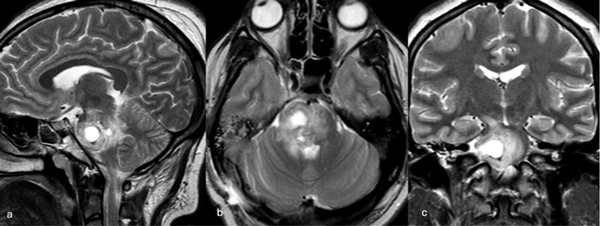

Caso 2: cavernoma pontino

Una paciente femenina de 28 años, sin antecedentes de sangrado previo, debutó con cefalea, náuseas y vómitos, asociado a diplopía secundaria a una parálisis del VI par derecho. La RM de encéfalo evidenció una malformación cavernomatosa centrada en puente y el pedúnculo cerebeloso medio derecho (Figura 3). Un mes después del sangrado, se realizó una exéresis de la lesión mediante un abordaje retrosigmoideo ampliado a través del pedúnculo cerebeloso medio (Figura 4), logrando una exéresis completa (Figura 5). Tras el procedimiento, la paciente evolucionó con hemihipoestesia del hemicuerpo izquierdo, sin otros síntomas agregados.

Figura 3. RM preoperatoria de encéfalo. Se evidencia una lesión única intraaxial centrada en puente y pedúnculo cerebeloso derecho, sugerente de un cavernoma roto. A, B y C) Imágenes ponderadas en T2 en cortes sagital, axial y coronal, respectivamente, donde se observa un importante hiperintensidad perilesional, sugerente de edema.

Figura 4. Imágenes intraoperatorias bajo microscopía. Abordaje retrosigmoideo ampliado a derecha, con ruta de ingreso transpedúnculo cerebeloso medio. A yB) Corticotomía en pedúnculo cerebeloso medio. C) Identificación y resección en bloque de la malformación cavernomatosa. D) Revisión del lecho, sin remanente.

Figura 5. RM postquirúrgica de encéfalo. Se evidencia una exéresis completa con hiperintensidad en T2 en regresión. A, B y C) Imágenes ponderadas en T2 en cortes coronal, axial y sagital, respectivamente.